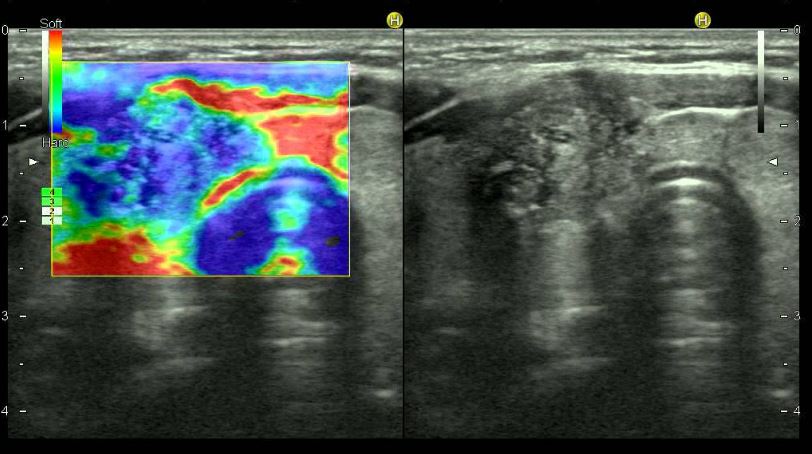

Elastografía

La elastografía con ecografía, o elastografía transitoria, es una técnica que utiliza ultrasonido para medir la rigidez de los tejidos, principalmente el hígado, en tiempo real.